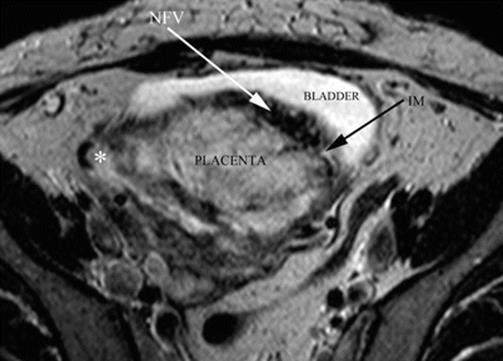

14.6 Placental MRI: Depth of Invasion

During a second stage, pMRI was requested to know the depth of placental invasion [10], especially to know whether the bladder is invaded. But bladder invasion is a vascular phenomenon, completely different from tissue invasion than neoplasia. In these cases, the placenta takes irrigation from the external layer of the bladder, but the state of uterine-bladder interface may be different according to thinning of myometrium, bladder wall, fibrous tissue between them or a combination of all these variables. For some authors, when the bladder is compromised, this is a formal indication to leave the placenta in situ, but this is not a really mandatory option. Placental MRI allows seeing this interface in great detail in axial T2 slices. When this series (axial T2) is performed perpendicularly to the posterior bladder wall, the anatomy of the placental-bladder interface is not distorted and shows a clear anatomy [13]. This interface can be distorted by peripheral circulation in a placental surface (engorged superficial vessels and lagoons) or by the presence of newly formed vessels between the placenta and the bladder. The presence of circular hypointensive signals (newly formed vessels) in the lower and posterior part of the bladder (cervicotrigonal area) is a reasonable sign of a very difficult dissection [13].

Axial MRI T1 image: axial slices made perpendicular to the posterior bladder wall are the most useful to see a vesical invasion. In this case, fibrous adherence between bladder and anterior myometrium is seen. White arrows: newly formed vessels. AIP type 2 (percreta)

Fig. 14.16

Axial MRI T2 image: white arrow, newly formed vessels between uterus and the bladder. Black arrow: interrupted myometrium. AIP type 2 (percreta) myometrial-bladder interphase is completely distorted